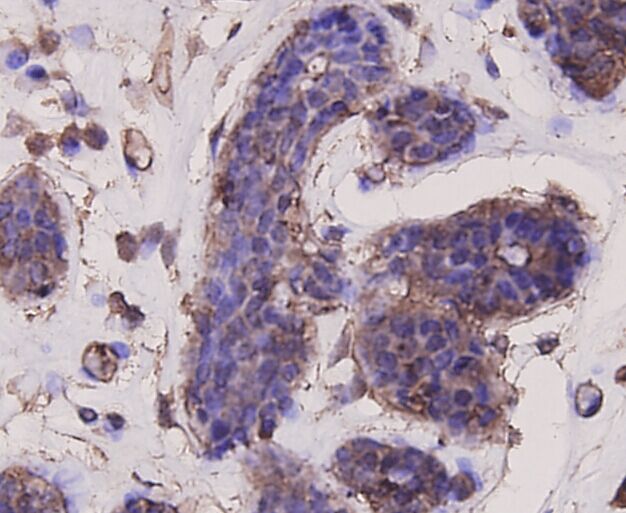

ApplicationsFlow Cytometry, Western Blot, ImmunoCytoChemistry, ImmunoHistoChemistry

- Antibody SpecificityThis antibody detects endogenous levels of AKT1 and does not cross-react with related proteins.

- ApplicationsFlow Cytometry, Western Blot, ImmunoCytoChemistry, ImmunoHistoChemistry

- Scientific DescriptionMouse monoclonal antibody to AKT1

![IHC-P analysis of human prostate carcinoma section using GTX02583 AKT1 antibody [rAKT1/2491].](https://www.genetex.com/upload/website/prouct_img/normal/GTX02583/GTX02583_20210319_IHC-P_1_w_23053122_113.webp)